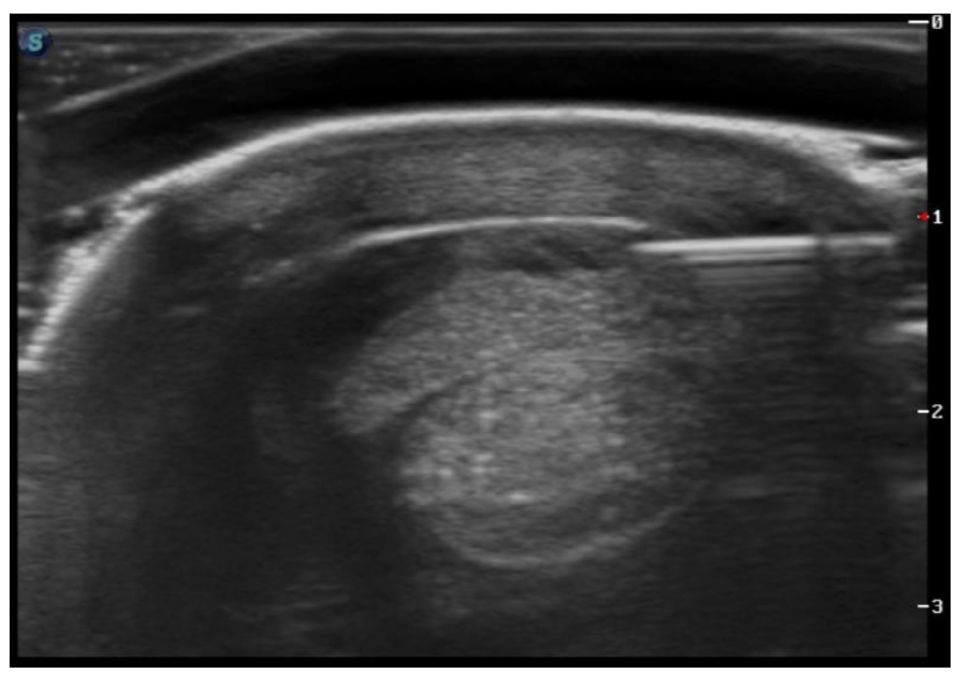

There are also different methods of implanting the stem cells into the horse at specific areas of interest. Dr. Davis explained, “If we were treating a meniscal injury or cartilage damage in a joint, implantation would be as simple as a joint injection technique. If you are going to implant cells into an injured tendon or ligament, then we will most often do an ultrasound guided technique where we watch and direct the needle precisely into the lesion so we can put these regenerative cells right into the damaged area.”

In order to treat a horse with Platelet Rich Plasma, the veterinarians at PBEC are able to take a sample of the horse’s blood and concentrate the platelets in a high-speed centrifuge on-site. This harvest and processing procedure takes approximately 30 minutes. The concentrated platelet rich sample is injected back into the horse at the specific area of injury using sterile technique and guided by ultrasound.